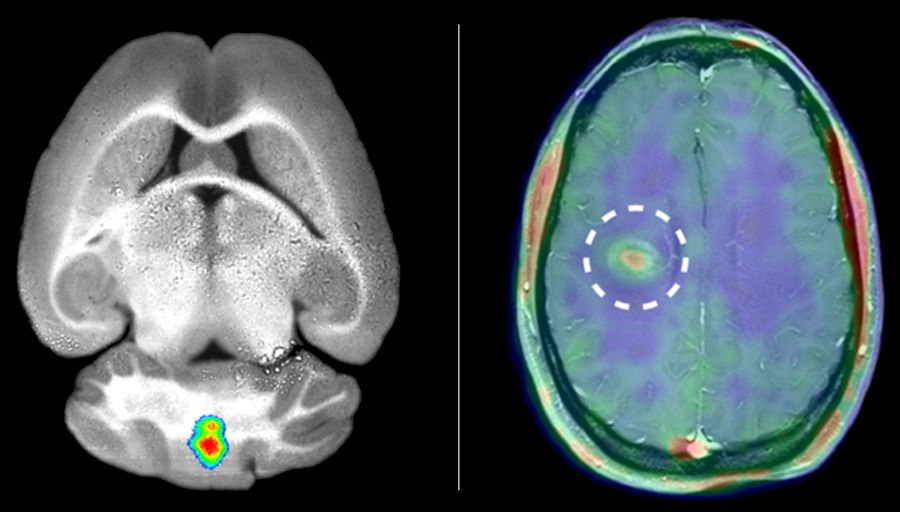

Die Blut-Hirn Schranke besteht aus einer Endothelzellschicht, der darunter liegenden Basalmembran und der parenchymalen Barriere/Glia Limitans. Es ist bekannt, dass Matrixmetalloproteinasen (MMP)-2 und MMP-9 für die Leukozytenpenetration dieser Barriere bei einer Neuroinflammation essentiell sind und deren funktionale Integrität beeinflussen. Trotzdem ist die Datenlage dazu rar, wie MMP-2 und MMP-9 die prenchymale Barriere exakt beeinträchtigen.

Mithilfe eines maßgeschneiderten, sensitiven, labelfreien Massenspektrometrie-basierten Sekretom-Ansatzes identifizierten die Studienautorinnen und -autoren 119 potenzielle MMP-9 und 21 MMP-2 Substrate an der Oberfläche von primären Astrozyten. Es wurden sowohl bekannte Substrate indetifiziertt als auch eine breite Palette von zuvor unbekannten MMP-abhängigen Events, welche an Zell-Zell- und Zell-Matrix-Interaktionen beteiligt sind. Anhand eines Tiermodells für Neuroinflammation zur Bewertung der beeinträchtigten astroglialen Barriere wurden MMP-Substrate in vivo bestätigt und einige davon auch in menschlichen Multiple-Sklerose-Proben nachgewiesen, darunter VCAM-1 und NrCAM.

The blood-brain barrier is composed of an endothelial cell layer, its underlying basement membrane and the parenchymal border/glia limitants. While matrix metalloproteinases (MMP)-2 and MMP-9, are key for leukocyte penetration of this border in neuroinflammation and its functional integrity, data are sparse as to precisely how MMP-2 and MMP-9 affect barrier properties.

Using a tailored, sensitive, label-free mass spectrometry-based secretome approach we identify 119 MMP-9 and 21 MMP-2 potential substrates at the surface of primary astrocytes. These include known substrates and a broad spectrum of previously unknown MMP-dependent events involved in cell-cell and cell-matrix interactions. Using an animal model of neuroinflammation to assess compromised astroglial barrier function, MMP substrates were confirmed in vivo and some verified in human multiple sclerosis samples, including VCAM-1 and NrCAM.